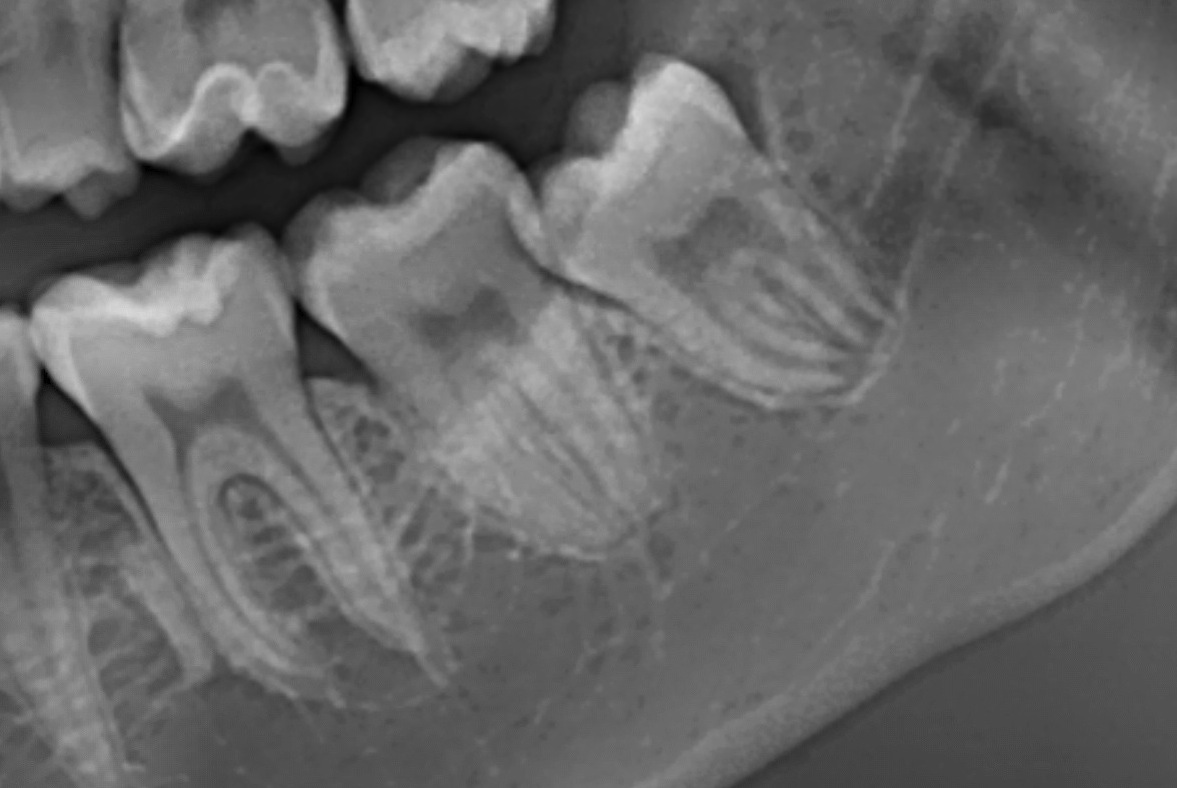

Terzo molare inferiore sinistro a contatto con il canale mandibolare

BlogDente del giudizio

Lesioni del nervo alveolare inferiore a seguito di estrazione del dente del giudizio